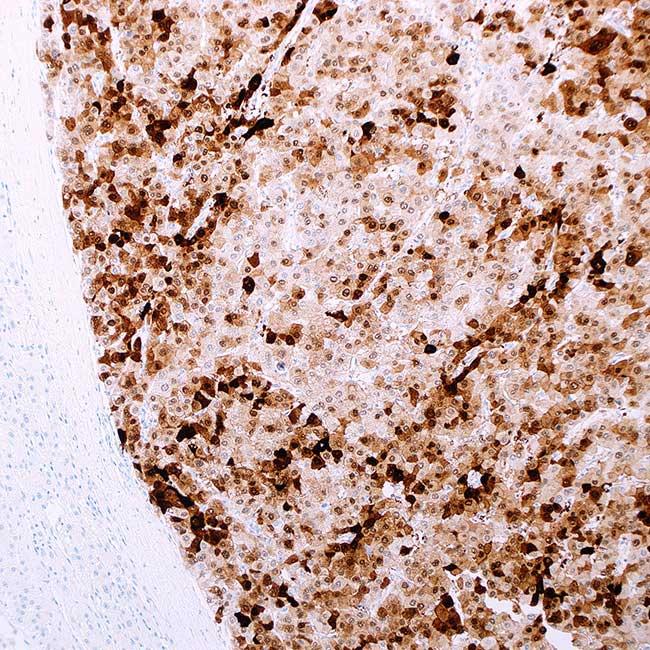

高度に保存されたシャペロンタンパク質であるHeat Shock Protein 70ファミリーは、温度ショック、低酸素、酸化ストレス、pH 変化などのストレス要因にさらされると発現が増加します1。 そして、他の機能の中でも特に、タンパク質のミスフォールドを修復し、タンパク質の凝集を防ぐことにより、細胞の生存を促進します1。 同様に、腫瘍細胞においても、肝細胞癌におけるHeat Shock Protein 70 の過剰発現で実証されているように、このメカニズムを利用して生存上の優位性を検証することができるでしょう1-5。